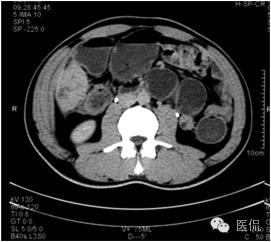

平扫示肝下缘局部隆突,密度减低,内部密度不均,隐约见分隔影,其下缘与升结肠界线消失,肠壁增厚、模糊。